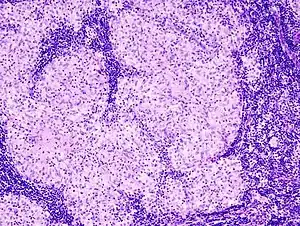

The characteristic morphological element is the tuberculous granuloma (caseating tubercule). This consists of giant multinucleated cells and (Langhans cells), surrounded by epithelioid cells aggregates, T cell lymphocytes and fibroblasts. Granulomatous tubercules eventually develop central caseous necrosis and tend to become confluent, replacing the lymphoid tissue.[8][9]

Tuberculous lymphadenitis is popularly known as collar stud abscess, due to its proximity to the collar bone and its superficial resemblance to a collar stud, although this is just one of the five stages of the disease. One or more affected lymph nodes can also be in a different body part, although it is most typical to have at least one near the collar bone.The characteristic morphological element is the tuberculous granuloma (caseating tubercule): giant multinucleated cells (Langhans cells), surrounded by epithelioid cells aggregates, T cell lymphocytes and few fibroblasts. Granulomatous tubercules evolve to central caseous necrosis and tend to become confluent, replacing the lymphoid tissue.[13][14]